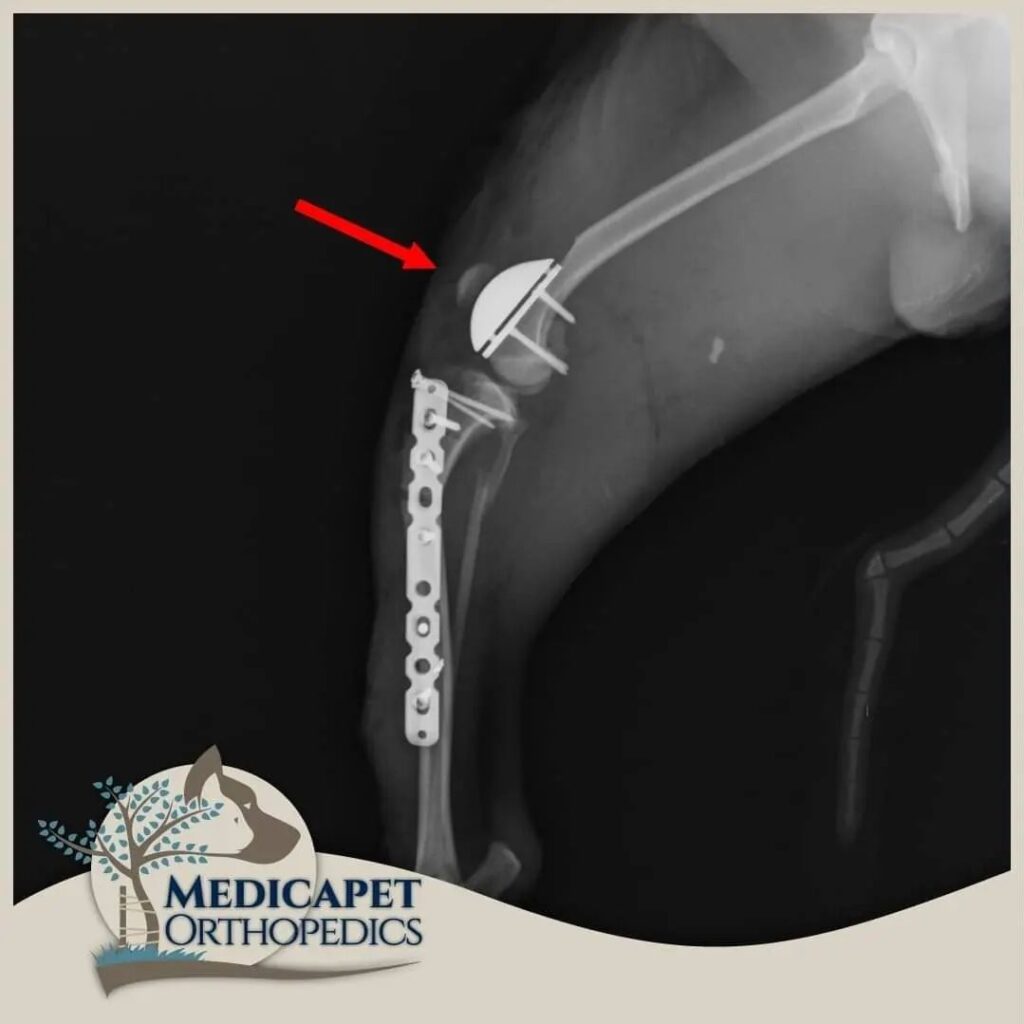

Kaval ve uyluk kemiklerinde ileri derecede eğrilik olan köpeklerin bu kemiklerinin aynı doğrultuya getirilmesini amaçlayan ve düzeltme osteotomileri ile bu kemiklerin doğru pozisyonda yeniden şekillendirildiği işlemlerdir. Daha çok ileri derecede deformasyon olan olgularda uygulanır. Yeniden şekillendirilen uzun kemikler son hallerinde iyileşebilmeleri için plak ve vidalarla sabitlenirler.

PGR (Patellar Groove Replacement)

Aşırı derecede hasar almış Patellar Oluk durumlarında bu oluğun bir protezle değiştirilmesi gerekir. Bu amaçla yüksek teknoloji ile üretilmiş doku uyumlu protezler kullanılır. Türkiye’nin ilk PGR operasyonu merkezimizde yapılmıştır. Şu anda da gerekli vakalarda başarı ile uygulanmaya devam edilmektedir.